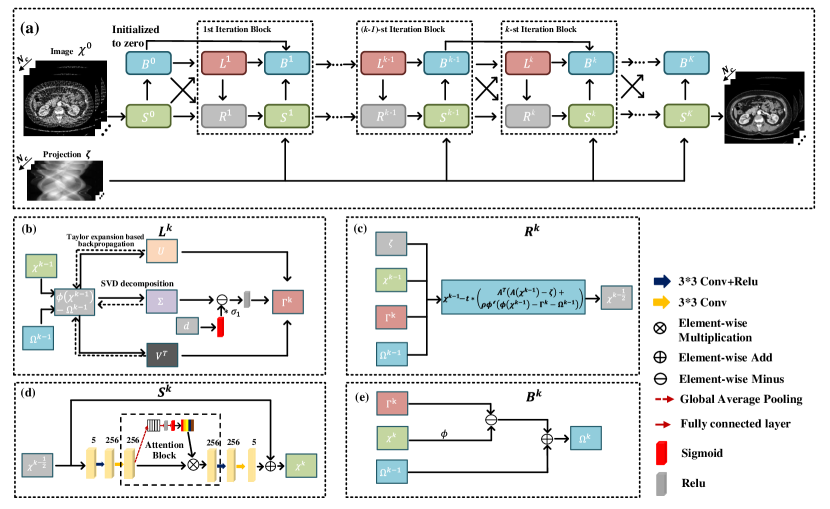

In our proposed SOUL-Net, the above iterative procedure is unrolled into a neural network, whose general architecture and components are illustrated in Fig. 1. In the unrolled -th iteration block shown in Fig. 1(a), there are four main modules: low-rank module , reconstruction module , sparse module and Lagrangian multiplier module . Each module corresponds to a subproblem in Eq. (9). The structures of each module are illustrated in Fig. 1(b)-(e), respectively. Each module is elaborated in the following subsections.

II-A Low-Rank Module

The update of the low-rank module in Eq. (9a) is illustrated in Fig. 1(b). In the traditional SVT method, the selection of the threshold , which has a great impact on the final performance, is empirically set and time-consuming. To circumvent this obstacle, we introduce a Taylor expansion-based learnable threshold method [33] to solve the low-rank problem. This is shown as

II-B Reconstruction Module

Fig. 1(c) illustrates the reconstruction module in Eq. (9b). Since the projection and backprojection operations are usually time-consuming, compute unified device architecture (CUDA) is adopted to accelerate the computation of Eq. (9b) [36]. To avoid the suboptimal results caused by manual selection of parameters, in this part, parameters and are learned from the training data.

II-C Sparse Module

The update of sparse module in Eq. (9c) is illustrated in Fig. 1(d). Eq. (9c) is a standard norm problem that can be solved by a nonlinear method, and the solution is related to the specific form of the sparse transform. For instance, the solution of the widely used total variation (TV) norm problem [6] can be obtained using the Chambolle-Pock projection algorithm [37] as follows:

| (18) |

where is a nonlinear projection operator. To improve the performance, in our proposed SOUL-Net, an attention-based network is utilized to learn the nonlinear projection operator instead of the handcrafted sparse transform. As shown in the sparse module in Fig. 1(d), is fed into a two-layer convolutional neural network (CNN). Then, the obtained feature maps are scaled with the learned channel attention [38] and fed into another two-layer network. Finally, the output adds to complete the update of the sparse module.

The attention mechanism is widely used in medical imaging [39, 40], which identifies the parts of features that most contribute to the results. For spectral CT imaging, we introduce the channel attention mechanism [38] to better fuse the information across the energy bins and learn the nonlinear projection operator. The attention block is shown in Fig. 1(d). The sizes of the convolution kernels are set to .

II-D Lagrangian Multiplier Module